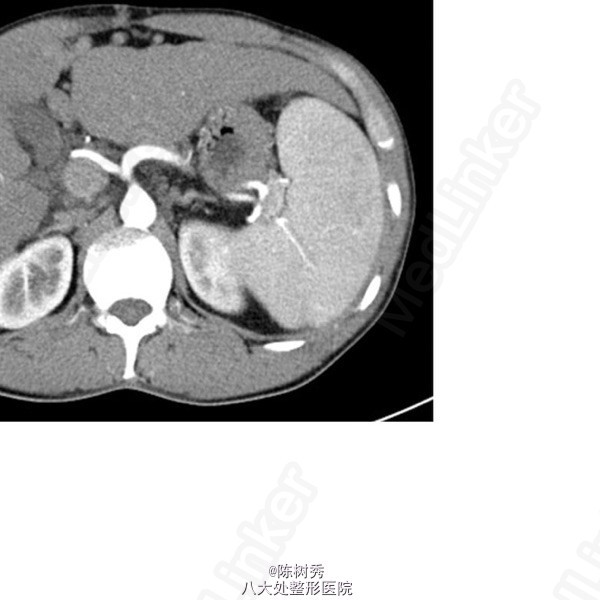

专 科 情 况 腹部平坦,未见胃肠型及蠕动波,腹壁静脉曲张,脐上曲张静脉向上走行,脐下曲张静脉向下走行,全腹软,无压痛、反跳痛,肝脏触诊正中线剑突下5cm可触及肝脏下缘,质中,无压痛,右锁骨中线肝脏不能触及,在左锁骨中线肋下6cm处可触及肿大的脾脏,质中,无压痛,Murphy(-),肝区、肾区扣痛(-),移动性浊音(-),肠鸣音3次/分。 辅 助 检 查 胃镜:食管中下段见4条曲张静脉,其中2条曲张静脉呈串珠样,红色征阳性,直径约0.5cm,曲张静脉延伸至本门口,胃底未见曲张静脉,胃底体散在充血斑,胃窦粘膜花斑充血水肿,红白相间,红相为主,散见多个片状充血斑;提示:食管静脉曲张,胆汁反流性胃炎。 腹部增强CT+门静脉三维重建:肝脏体积增大,左右叶比例失调,边缘欠光整,可见多发小结节样凸起,肝脏内部强化欠均匀。胆囊张力不大,胆囊壁不厚。左肾上腺结合部饱满,右肾上腺大小形态密度未见明显异常。腹膜后及肠系膜根部多发小淋巴结。三维重建:门静脉主干及左、右支增宽,主干直径约2.1cm。脾静脉迂曲增粗,周围多发侧枝循环。食管、胃底静脉及腹壁静脉曲张,附脐静脉增粗。可见多发侧枝循环。脾动脉迂曲,余腹部各动脉未见明显异常,提示:肝硬化伴门脉高压改变;脾脏增大;脾动脉迂曲;脾静脉迂曲增粗,周围多发侧枝循环;食管、胃底静脉及腹壁静脉曲张,附脐静脉增粗;左肾上腺结合部饱满。

诊断:酒精性肝硬化 失代偿期 门静脉高压症 食管静脉曲张 重度 破裂出血 门静脉高压性胃病 脾功能亢进症 腹水 全麻下行“腹腔镜下粘连松解,脾切除,胃底贲门周围血管离断术,食道下段、胃底切除术”,手术过程顺利。